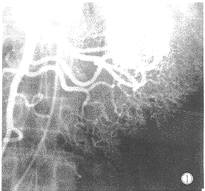

2.纖維十二指腸鏡、纖維小腸鏡檢查及選擇性動脈造影術.可提高小腸腫瘤的診斷率。

空腸和迴腸的腫瘤占胃腸道腫瘤的1%~5%.主要是良性的,其中包括平滑肌瘤,脂肪瘤,神經纖維瘤和纖維瘤,所有這些贅生物都可能引起症狀並需要手術.息肉可見於小腸,但更多見於結腸.在小腸中55%的血管瘤病例是多中心的.遺傳性出血性毛細血管擴張(Rendu-Osler-Weber綜合徵)是一種先天性進行性疾病,具有形成擴張的內皮腔隙的傾向.血管瘤可出血或形成腸套疊.血管發育不良或動靜脈畸形是衰老的後果,多見於小腸的遠側端或盲腸。

腺癌不常見.通常該腫瘤發生於空腸近側端,可引起輕微的症狀.在有克羅恩病的情況下,腫瘤多發生於腸道遠側端和旁路或發炎的腸袢.腺癌在小腸克羅恩病患者中較結腸克羅恩病患者更為常見.發生於迴腸的原發性惡性淋巴瘤可形成長而僵硬的腸段.小腸淋巴瘤常見於熱帶口炎性腹瀉患者,小腸特別是迴腸是類癌的第二個好發部位(僅次於闌尾).50%的病例可出現多發性腫瘤.在直徑>2cm的惡性腫瘤中,80%患者至手術時已發生局部轉移或肝轉移.約30%的小腸類癌可引起梗阻,疼痛,出血或類癌綜合徵.治療為手術切除,可能需要多次手術。